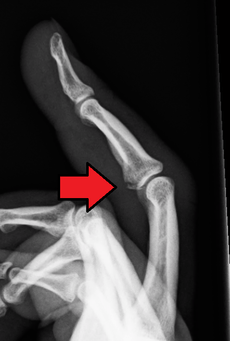

![]() Avulsion fracture of the proximal metacarpal on the volar side |

An avulsion fracture is a bone fracture which occurs when a fragment of bone tears away from the main mass of bone as a result of physical trauma. This can occur at the ligament due to the application forces external to the body (such as a fall or pull) or at the tendon due to a muscular contraction that is stronger than the forces holding the bone together. Generally muscular avulsion is prevented due to the neurological limitations placed on muscle contractions. Highly trained athletes can overcome this neurological inhibition of strength and produce a much greater force output capable of breaking or avulsing a bone.